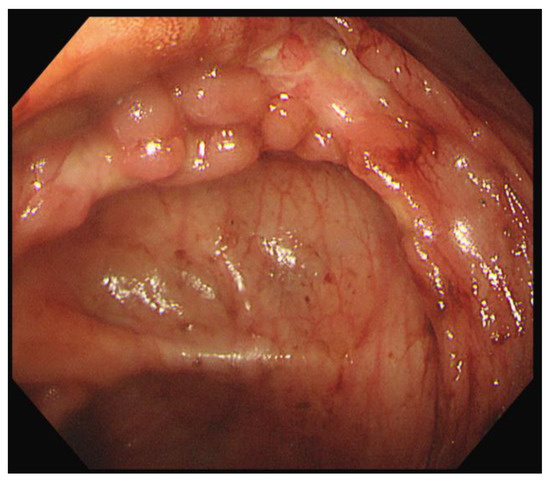

Capsule endoscopy was performed to evaluate mucosal lesions in the small intestine. Three or more ulcerations were confirmed, and fresh blood due to active bleeding was observed in the distal small intestine (Figure 5).

Figure 5.

Capsule endoscopy revealed three or more ulcers of various sizes (a) and active bleeding in the distal ileum (b).